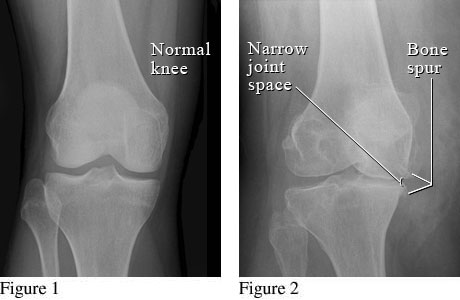

I have been reviewing the material for each class, specifically radiology, since it is the first exam next week. This is the third radiology class of the program. The first was normal radiographic anatomy; the second focused on the physics of radiology; and the third class is focused on diagnosis of joint pathology. The first step in diagnosing abnormalities on film is to know what normal looks like (hence why it is the first radiology class we take). If the film is abnormal, the next step is to figure out what is abnormal about it. From there, a diagnosis can be hypothesized. Each condition has its own defining characteristic such as narrowing joint space and bony spurs for degenerative joint disease (DJD).

Image Source: WebMD.com